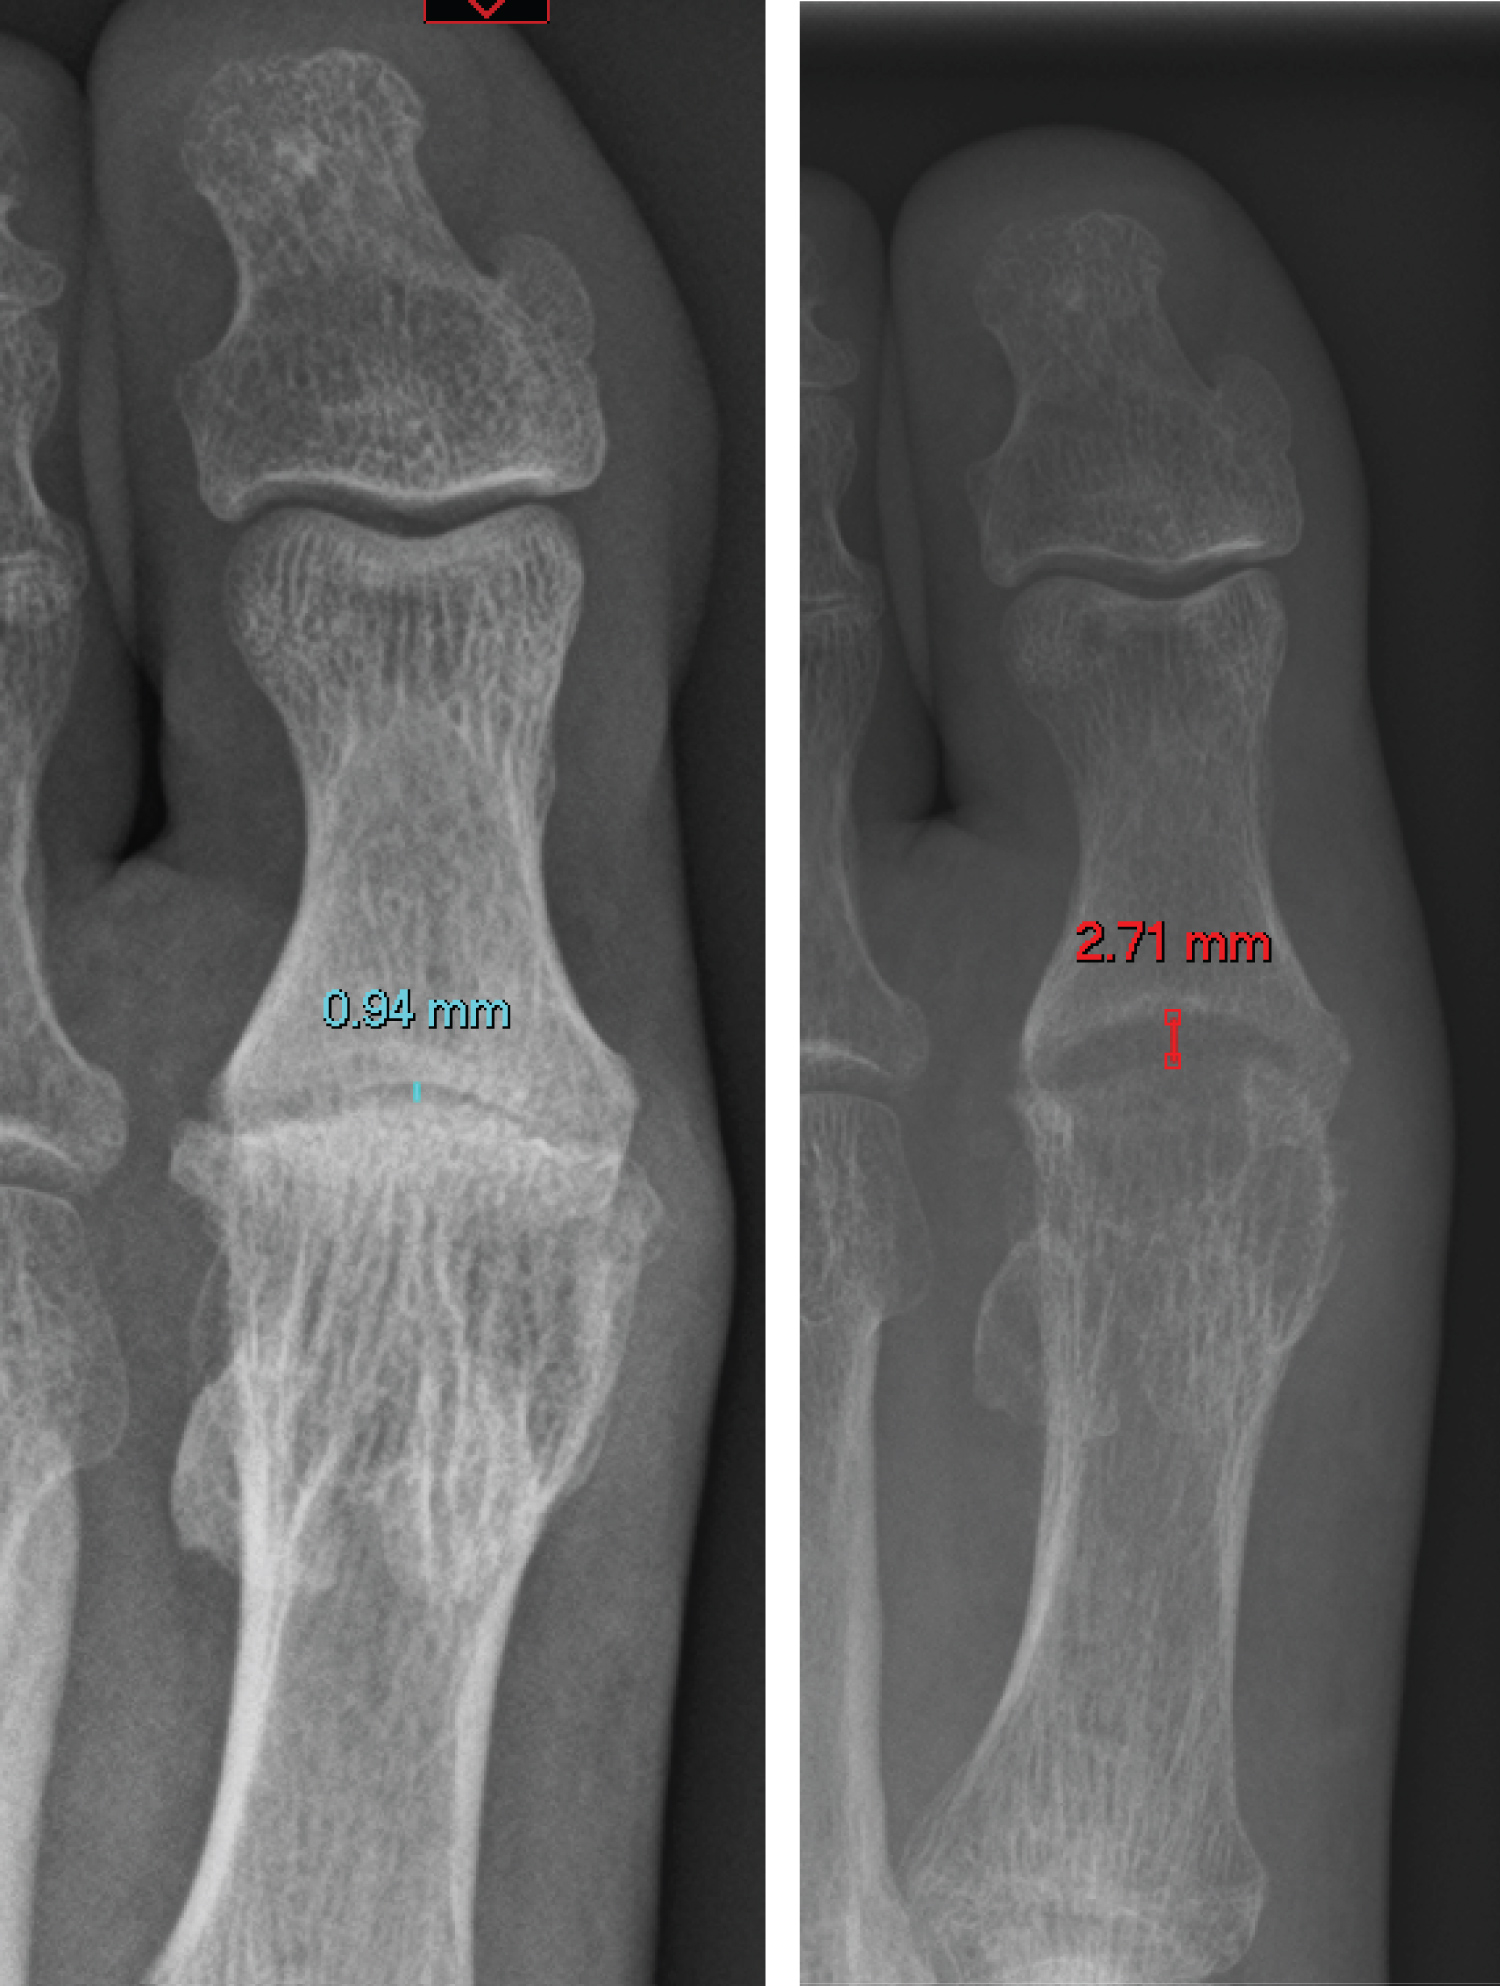

A total of 19 SCI operations were conducted over the study period, 9 right toes and 10 left toes. These were from 16 patients, 11 female and 5 male, who had a mean age of 53 years (range 37 - 64). Thirteen toes were classified as (C&S) grade 4 and 6 were classed grade 3. See Figure 2 for a typical preoperative and postoperative radiograph.

Figure 2: preoperative and postoperative radiograph demonstrating increased joint space. The cavity in the metatarsal head housing the implant is also visible on plain films. View Figure 2